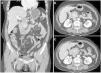

El linfoma pancreático primario es una enfermedad pancreática extremadamente inusual que requiere de un alto nivel de sospecha para ser diagnosticado. La diferenciación de la neoplasia pancreática maligna comúnmente encontrada, es decir, adenocarcinoma, es crucial, dado el potencial para ser manejado de manera no quirúrgica. Las características de imagen, aunque complejas, pueden sugerir el diagnóstico de linfoma pancreático primario. Estas incluyen una voluminosa masa tumoral bien delimitada en la cabeza del páncreas, ausencia de dilatación de conducto pancreático marcada, lo cual está asociado con linfadenopatía peripancreática confinada, pero no con linfadenopatía superficial o mediastinal, ni con afectación hepática o esplénica. La tomografía computarizada (TC) puede mostrar características hipodensas homogéneas en la fase venosa portal (fig. 1) y la imagen por resonancia magnética (IRM) puede mostrar características de señal baja en imágenes ponderadas en T1, con contraste sutil, o características de señal heterogénea con imágenes ponderadas en T2. Finalmente, una restricción de la difusión observada en una técnica de difusión (DWI, por sus siglas en inglés)/coeficiente de difusión aparente (ADC, por sus siglas en inglés) en IRM indica un alto grado de sospecha de linfoma pancreático primario (fig. 2).

IRM ponderada en T2 (T2W) coronal y axial donde se observa una masa en la cabeza pancreática (A-E-asterisco), con intensidad de señal intermedia, acompañada de linfadenopatía peripancreática justo por encima de la masa, presentando una señal ligeramente menos intensa que la masa (A-punta de flecha). La masa presenta características de señal hipointensa en las imágenes sin contraste ponderadas en T1W en fase y fuera de fase (B-C) y presenta un contraste ligeramente resaltado (D-asterisco). Nótese la permeabilidad de la arteria mesentérica superior y de la vena esplénica (D-flechas cortas) y el conducto pancreático ligeramente dilatado en la imagen T1W post contraste (D-flechas largas). Finalmente, las imágenes DWI axial y ADC correspondientes muestran restricción de difusión homogénea de la masa primaria (F-G-asterisco).